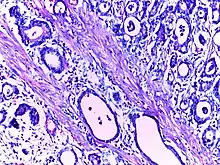

![]() | Squamous cell carcinoma of lung | Micrograph of squamous Cell Carcinoma Lung. A lobule of polygonal squamous cells with moderate amount of eosinophilic cytoplasm and hyperchromatic nuclei are seen. The islands show abnormal keratinization in the form of epithelial pearls in the centre. These epithelial pearls are whorls or eddies of malignant cells with pink keratin in the centre. | Category: Histopathology of squamous cell carcinoma of the lung | Squamous cell carcinoma of lung |